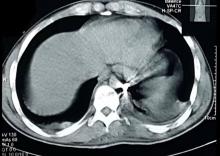

This is the case of a 24-year-old male patient who was involved in a blast injury. Among his multiple traumas was a metallic foreign body abutting the aorta in the left pleural cavity associated with the small hemothorax. Indications to remove the shrapnel included: proximity of the metallic shrapnel to a major vessel, shrapnel larger than 2 cm, and sharp/jagged edges. VATS was utilized to extract the bullet from the pleural cavity. In the author's view, the use of VATS in a hemodynamically stable trauma patient is both safe and effective in removing metallic foreign bodies and shrapnel from the pleural cavity.